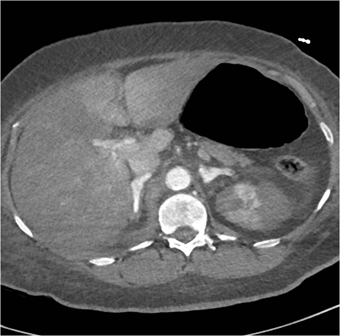

Based on these CT images the patient is likely to be

hypertensive